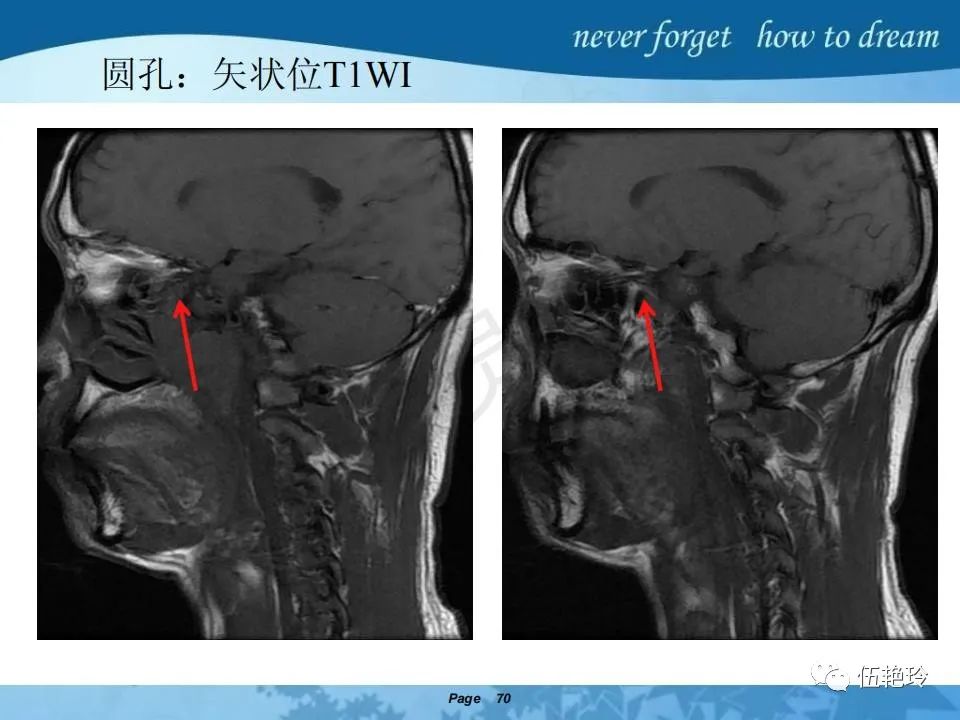

2.2 鼻咽特有的解剖途径:鼻咽癌原发灶循序进展的总途径:鼻腔(47.8%)→翼腭窝(15.2%)→ 眶下裂(3.2%)→眶尖(1.2%)→海绵窦(0.6%)。

2.31 向上颅内:①鼻咽顶壁→破裂孔(岩尖、斜坡)→蝶窦、海绵窦;②鼻咽顶壁→蝶骨基底部→蝶窦、海绵窦;③鼻咽侧壁→茎突前间隙→蝶骨大翼(卵圆孔)→海绵窦;④鼻咽侧壁→茎突前间隙→翼腭窝→ 颞下窝;⑤鼻咽前壁→鼻腔→翼突、翼腭窝→眶下裂→眶尖→海绵窦;⑥鼻咽前壁→鼻腔→上颌窦、筛窦;